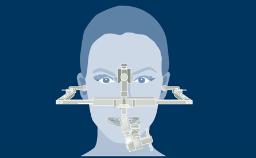

Independentemente da localização ou extensão do tratamento, o planejamento da terapia com implantes deve ser sempre orientado pela prótese. Isso garante que a instalação do implante atenderá às necessidades protéticas e será compatível com o resultado final desejado. Com o objetivo de alcançar um resultado ideal, o planejamento protético deve considerar todos os fatores protéticos relevantes e um modelo diagnóstico adequado como base para o planejamento específico das próteses sobre implante e implantes de suporte.

- explicar os benefícios de uma investigação diagnóstica em prótese para instalação de implantes